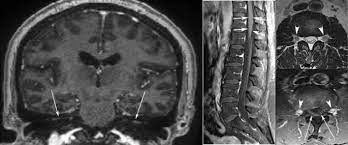

However, it can reveal nerve root enhancement and may be an effective diagnostic adjunct. The severity on mri does not correlate with severity of the clinical condition. Fisher syndrome, a clinical variant of guillain­ barre syndrome characterized by ataxia, are­ flexia, and ophthalmoplegia, brain stem lesions have been described with cranial mr.imaging (8). Its signs and symptoms are similar to those of other neurological disorders and may vary from person to person. Sagittal and axial post contrast t1 fs images shows smooth thickening and abnormal enhancement of the cauda equina and the ventral nerve roots. Moreover, gbs is also associated with any vaccination. Your doctor may then recommend: It is characterized by a triad of ophthalmoplegia, ataxia, and areflexia.

Clinical presentation is usually characterized by rapidly progressive, ascending, and symmetric paralysis of the extremities. Although no abnormalities were observed on brain and spinal magnetic resonance imaging and electroencephalography, peripheral nerve conduction velocity tests failed to evoke motor and sensory nerve action potentials. It is characterized by a triad of ophthalmoplegia, ataxia, and areflexia. Sagittal and axial post contrast t1 fs images shows smooth thickening and abnormal enhancement of the cauda equina and the ventral nerve roots. Scott olson / staff / getty images Moreover, gbs is also associated with any vaccination. Your doctor may then recommend: Mri is sensitive, but nonspecific, for diagnosis. The study findings are published in the journal neurological research. Mr imaging findings in eight patients (three male, five female; Immune checkpoint inhibitors (icis) have been increasingly used in the treatment of various types of tumors with favorable results. The most common result is a weakness and numbness that starts at the tips of the fingers and toes and spreads inward toward the body. Guillain barré syndrome (gbs) is characterized by demyelination and axonal degeneration of peripheral nerves.

Its signs and symptoms are similar to those of other neurological disorders and may vary from person to person. Sagittal and axial post contrast t1 fs images shows smooth thickening and abnormal enhancement of the cauda equina and the ventral nerve roots. Mri is sensitive, but nonspecific, for diagnosis. The diagnosis is usually established on the basis of symptoms and signs, aided by cerebrospinal fluid findings and electrophysiologic criteria. Clinical presentation is usually characterized by rapidly progressive, ascending, and symmetric paralysis of the extremities. Scott olson / staff / getty images Your doctor is likely to start with a medical history and thorough physical examination. It is the most common cause of rapidly progressive flaccid paralysis.

On csf analysis, the cell count is normal in 85% of patients, and high protein values are seen in 64%. Sagittal and axial post contrast t1 fs images shows smooth thickening and abnormal enhancement of the cauda equina and the ventral nerve roots. Clinical presentation is usually characterized by rapidly progressive, ascending, and symmetric paralysis of the extremities. Fisher syndrome, a clinical variant of guillain­ barre syndrome characterized by ataxia, are­ flexia, and ophthalmoplegia, brain stem lesions have been described with cranial mr.imaging (8). Typically, both sides of the body are involved, and the initial symptoms are changes in sensation or pain often in the back along with muscle weakness, beginning in the feet and hands, often spreading to the arms and upper body. Mr imaging findings in eight patients (three male, five female; With treatment, people may improve more quickly. However, it can reveal nerve root enhancement and may be an effective diagnostic adjunct. Your doctor may then recommend: The most common result is a weakness and numbness that starts at the tips of the fingers and toes and spreads inward toward the body. Moreover, gbs is also associated with any vaccination. Mri is sensitive, but nonspecific, for diagnosis. Immune checkpoint inhibitors (icis) have been increasingly used in the treatment of various types of tumors with favorable results.